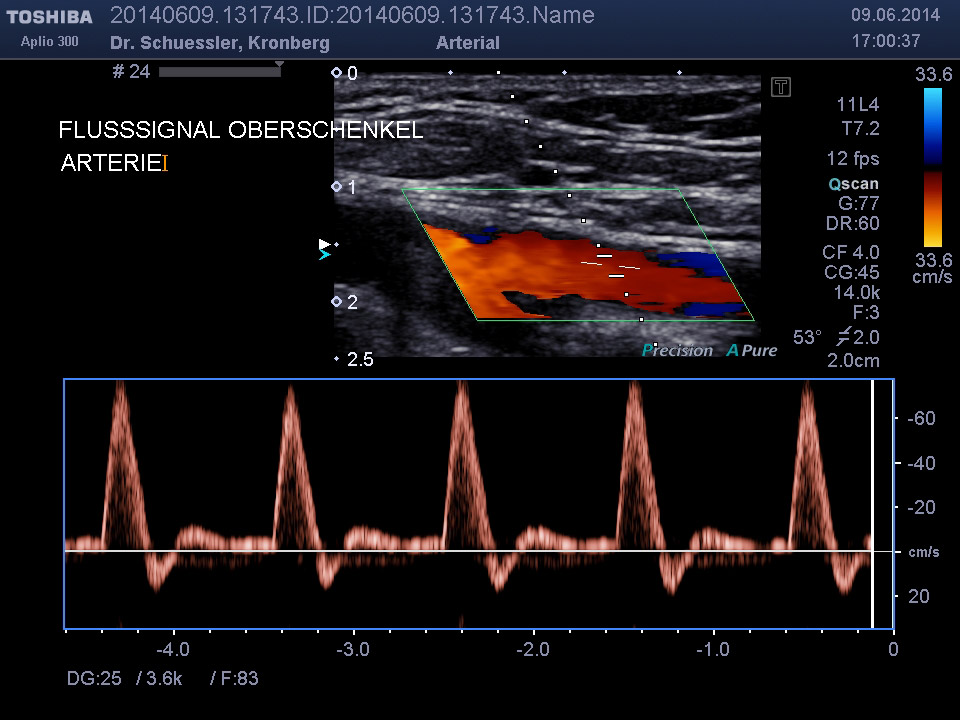

Die farbkodierte Duplexuntersuchung der Gefäße ist ein Ultraschallverfahren und gibt u.a. Auskunft über Verkalkungen, Einengungen, Verschlüsse oder Thrombosen im Bereich der Arterien und Venen.

Sie kann in allen Gefäßregionen des Körpers zur Anwendung kommen.

Die Untersuchung wird angewandt zur Diagnostik von Verengungen in den hirnversorgenden Arterien, Erweiterungen (Aneurysmen) oder Verengungen der Bauchschlagader, Verengungen der Nierenarterien bei Bluthochdruck,  Venenthrombosen und zur Bestimmung des Gefäßrisikoprofils.